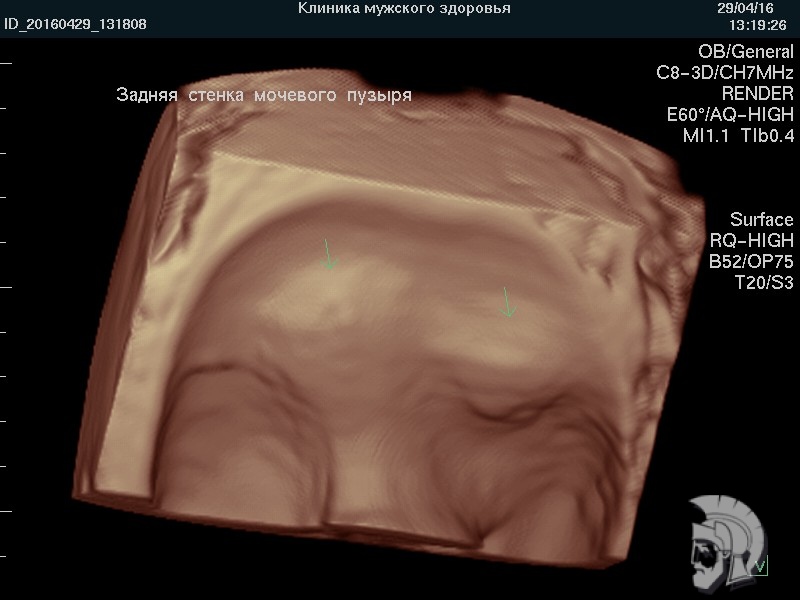

| 3D-фото мочевого пузыря. Определяется складчатость стенок мочевого пузыря. Матка и левый яичник указаны стрелками |